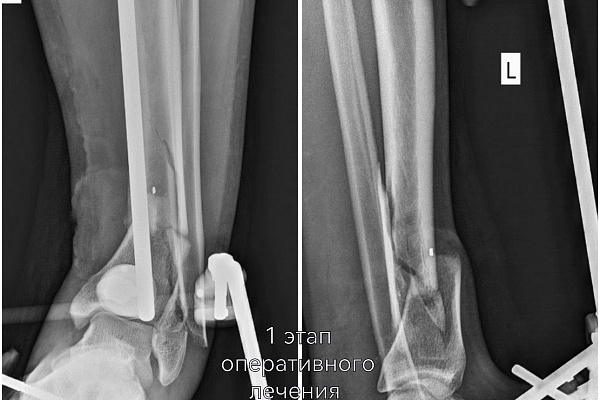

В экстренном порядке эффективно сработала команда опытных врачей травматологов-ортопедов Владимира Кельметра и Сергея Глиняного. На микрохирургическом этапе операции удалось восстановить целостность поврежденных сосудов и нервов. Кости голени зафиксировали с помощью модульной стрежневой системы.

Цель первого этапа хирургического лечения - жизнеспособность конечности – была достигнута. Цель второго этапа – опороспособность. К нему приступили, убедившись, что ранний послеоперационный период протекает благополучно, без осложнений.